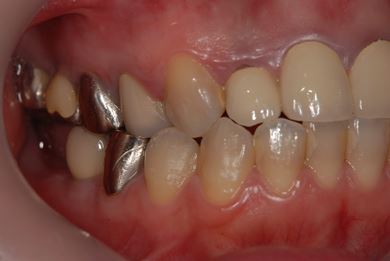

インプラントの症例写真 IMPLANT

インプラント治療

| 性別/年齢 | 女性 / 34歳 | ||||||||||||||||||||||||||||||||

| 主訴 | 左上奥の歯茎の腫れと、口臭などが気になっています。 | ||||||||||||||||||||||||||||||||

| 治療方針 | 右下奥欠損部分をインプラント治療にて機能的・審美的回復を行う。 | ||||||||||||||||||||||||||||||||

| 治療内容 | インプラント1本、メタルボンドセラミッククラウン1本 | ||||||||||||||||||||||||||||||||

| 総治療費 | 252,000円 | ||||||||||||||||||||||||||||||||

| 治療期間 | 4ヶ月 |